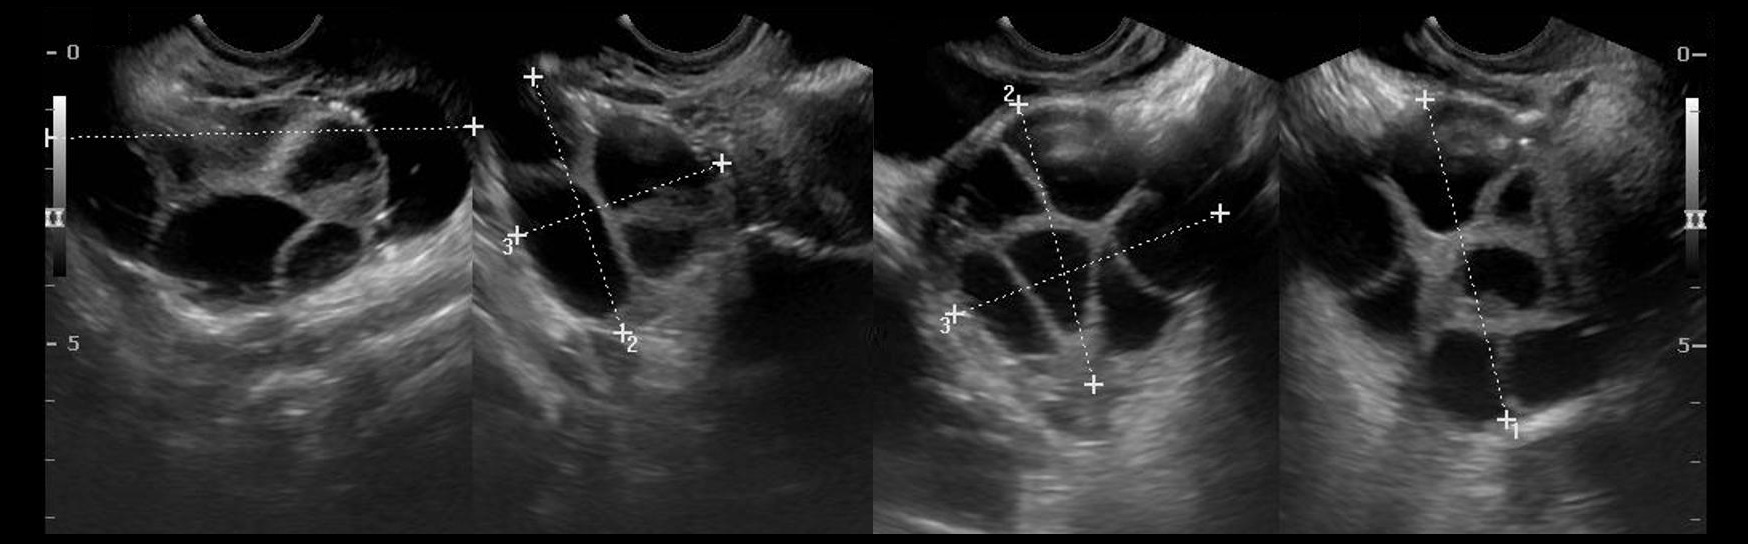

Гистологические изображения фолликулярной кисты яичника